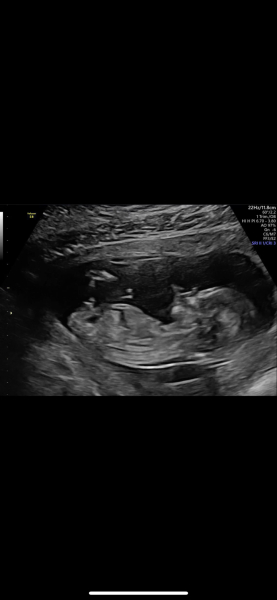

Thankyou!! 1st and 3rd are 14weeks. 2nd pic is 12+4. I don't have the 13+2 pic on my phone :) x

Gender at 14 weeks? Accurate?

Looks like a boy to me, congratulations! I think it's very likely it will be a boy, particularly if you had a private scan at 14 weeks too to tell you the sex.

It does look like Boy 💙 and sounds like everyone has been pretty certain.